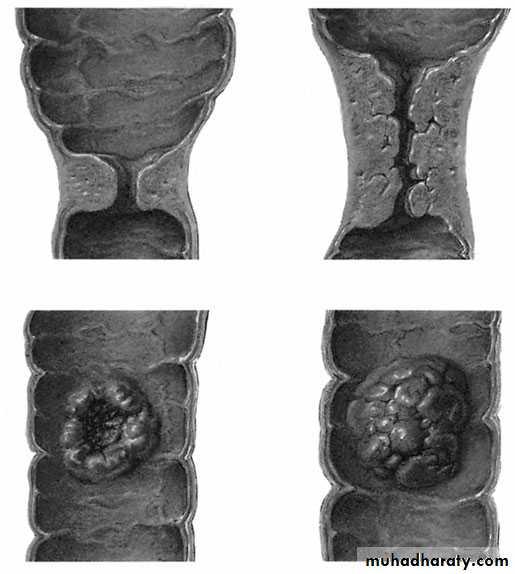

Adenocarcinoma of the colonPathologyMicroscopically, the neoplasm is a columnar cell carcinoma originating in the colonic epithelium. Macroscopically, the tumourmay take one of four forms (1) Annular; (2) tubular; (3) ulcer; (4) cauliflower. Type 4 is the least malignant form. It is likely that all carcinomas start as adenoma, the so called ‘adenoma–carcinoma sequence’.

The annular variety tendsto give rise to obstructive symptoms, whereas the others will present more commonly with bleeding. Tumours are morecommon in the left colon and rectum.